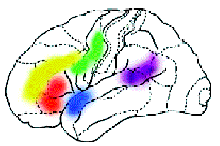

Исследования, проведённые в последние годы в Институте мозга человека Российской академии наук, позволили определить, какие области мозга отвечают за осмысление различных особенностей воспринимаемой человеком речи: за грамматику, синтаксис, орфографию и другие.

Область, отвечающая за определение грамматических характеристик слова

Зона, активная при необходимости использования кратковременной памяти

Зоны речевой моторики

Зоны первичной обработки цвета

Зоны, участвующие в обработке синтаксической структуры предложений

Зона орфографической обработки слов

Область, участвующая в сознательной и непроизвольной обработке смысла слов

Области, предположительно управляющие подавлением обработки речевых признаков в задаче на обработку физического признака слова, например цвета |

А теперь представьте, что человек выполняет какое-то сложное задание, требующее от него знания правил орфографии или логического мышления. При этом у него наиболее активно работают нервные клетки в области мозга, „ответственной“ именно за эти навыки. Усиление работы нервных клеток можно зарегистрировать с помощью ПЭТ по увеличению кровотока в активизированной зоне. Таким образом удалось определить, какие области мозга „отвечают“ за синтаксис, орфографию, смысл речи и за решение других задач. Например, известны зоны, которые активизируются при предъявлении слов, неважно, надо их читать или нет. Есть и зоны, которые активизируются, чтобы „ничего не делать“, когда, например, человек слушает рассказ, но не слышит его, следя за чем-то другим.